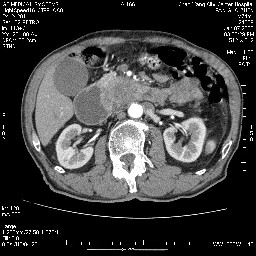

女,74岁,呕吐10余日

壶腹部的占位性病变,考虑为十二指肠癌并梗阻,但脾内多发性低密度区为转移吗?

还有胃、脾之间可见有侧支循环建立。左肾盂积水。

十二指肠水平段腔内占位伴梗阻,中等度较为均匀的强化,洗脱慢,区域淋巴结显示增多,符合腺癌表现。下腔静脉变异。

十二指肠降段扩张,水平段狭窄成鼠尾状,肠壁明显增厚,胰腺勾突增大成不均匀强化,其内可见低密度区,胆囊增大,1十二指肠水平段腺癌侵犯胰腺勾突可能大,2胰腺癌侵犯十二指肠(只有胆囊增大没有肝内外胆管扩张不好解释)代除外.

十二指肠降段扩张,水平段狭窄成鼠尾状,肠壁明显增厚,胰腺勾突增大成不均匀强化,其内可见低密度区,胆囊增大,1十二指肠水平段腺癌侵犯胰腺勾突可能大,2胰腺癌侵犯十二指肠 。

今日手术结果:胰腺钩突癌侵犯十二直肠,腹腔淋巴结转移.